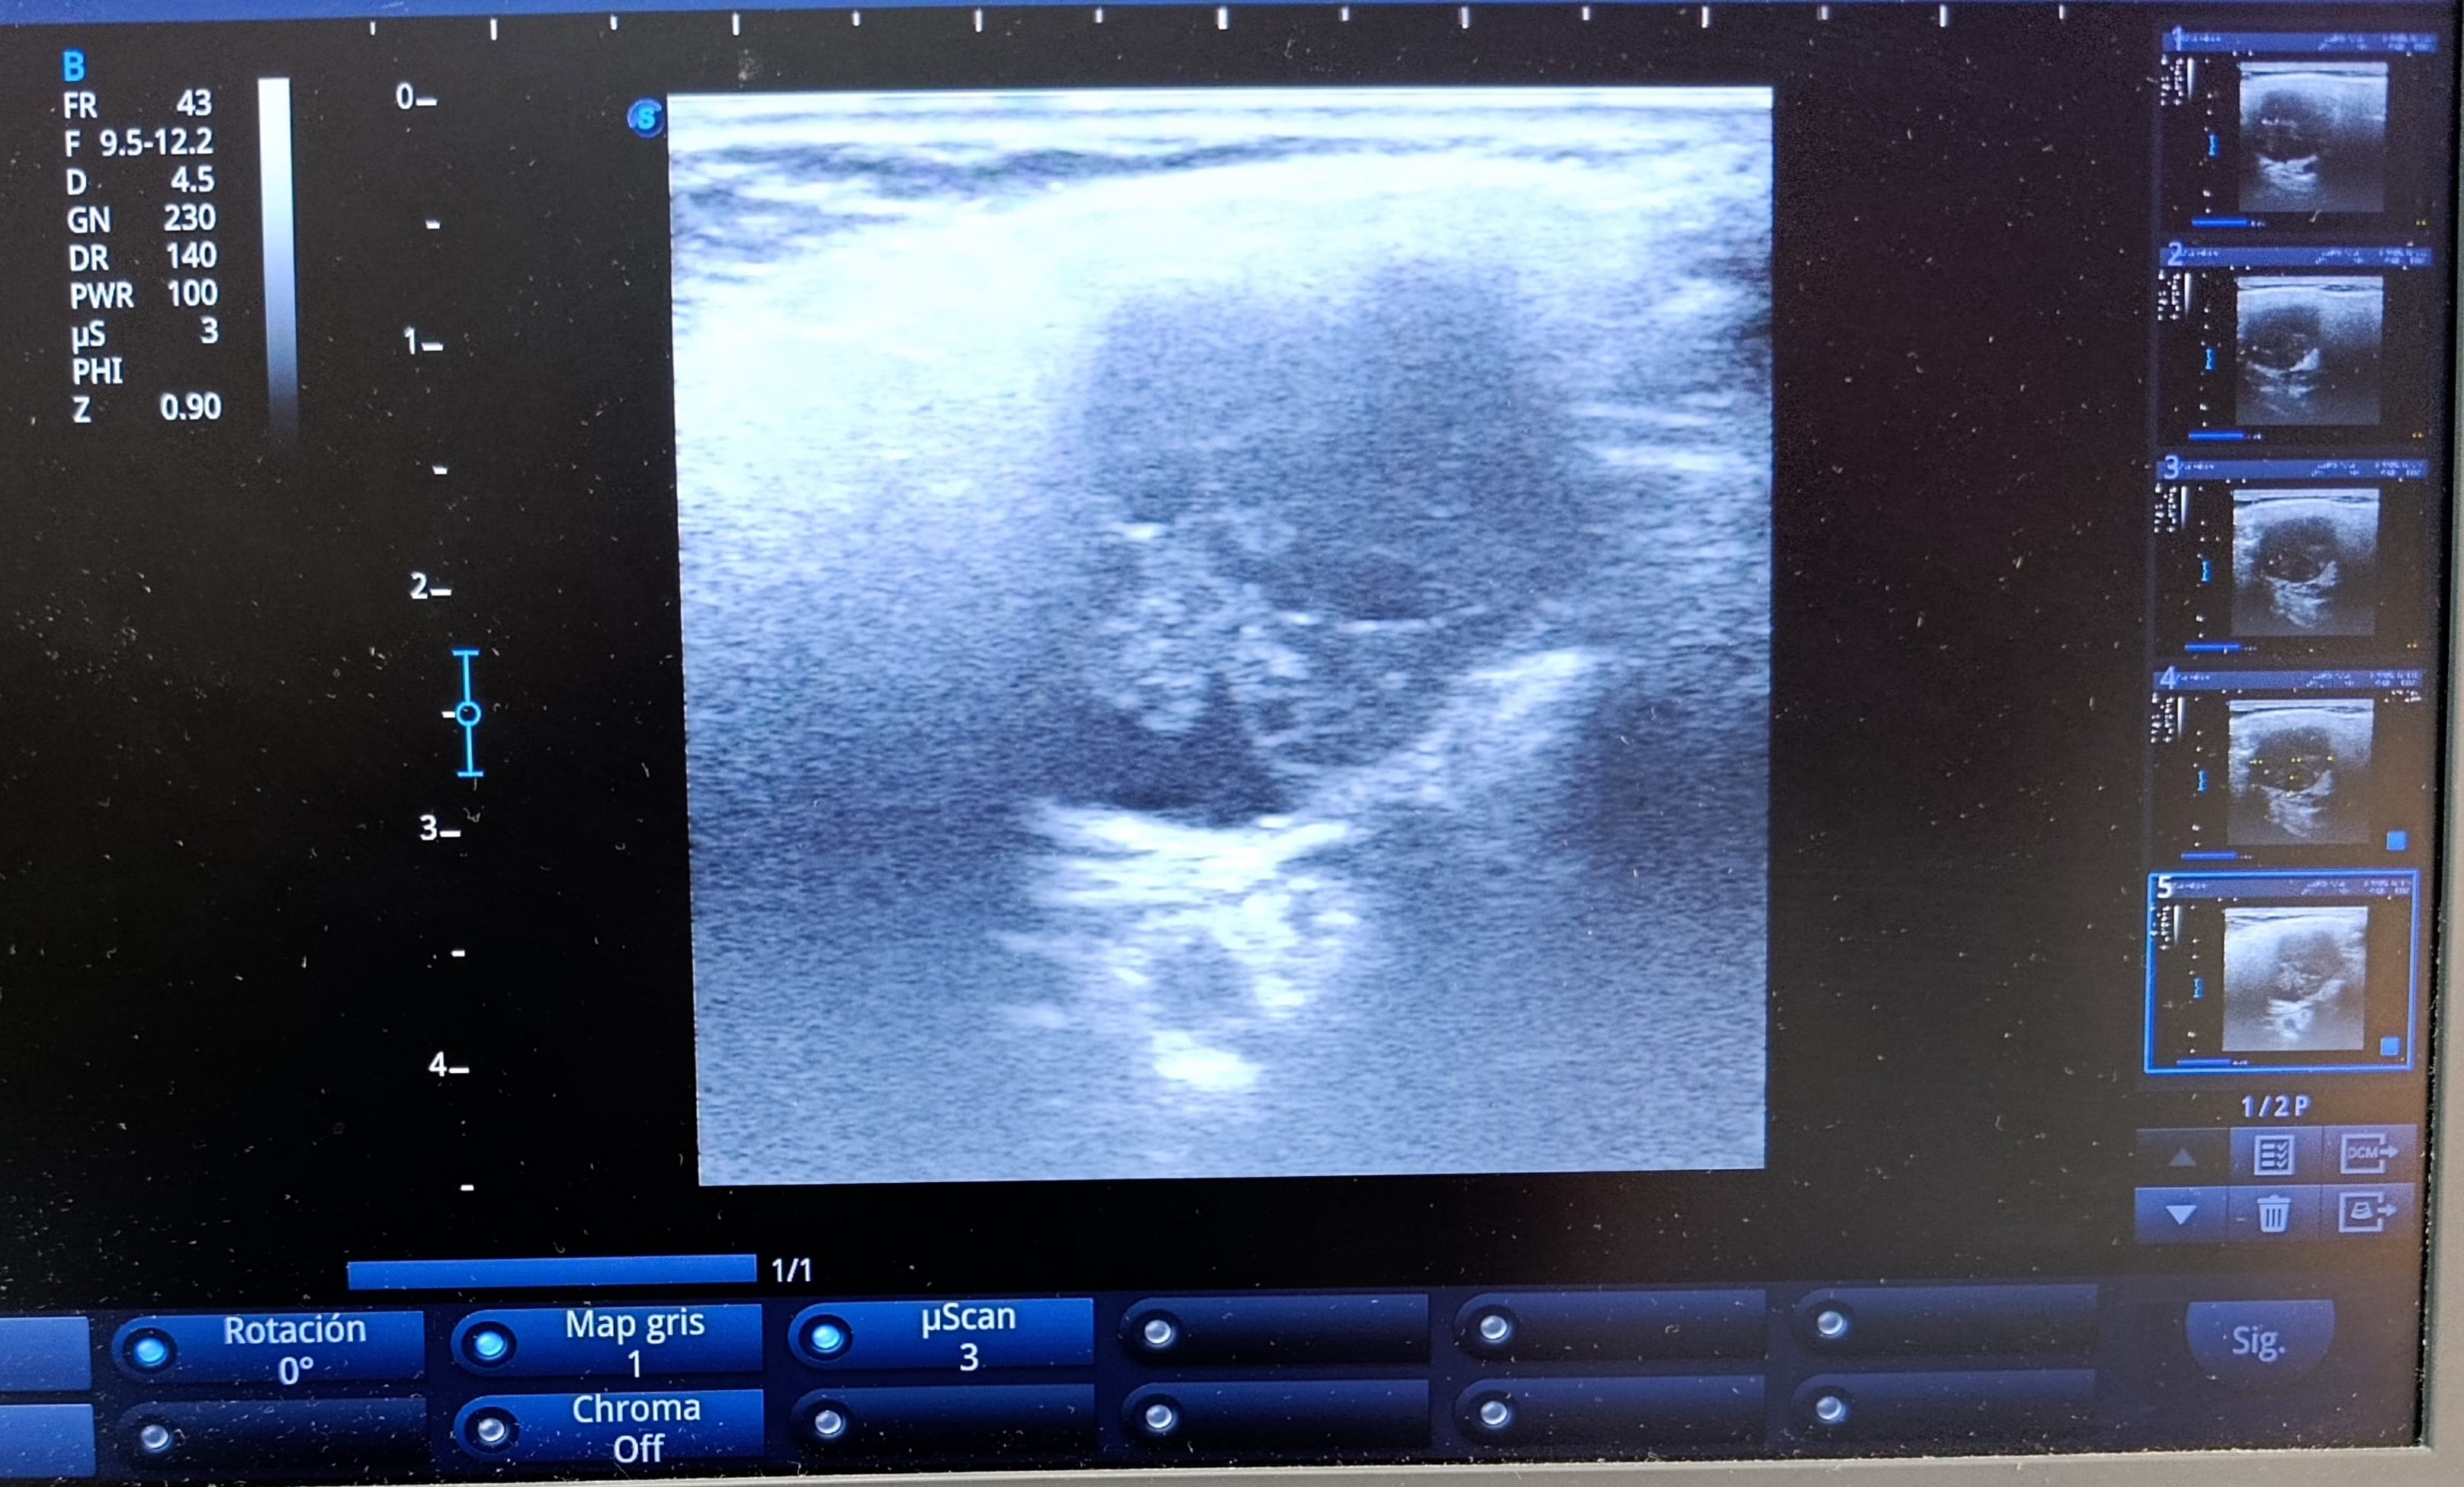

Realizamos ecografía clínica en consulta en región paratiroidea izquierda.

Hallazgos ecográficos

Ecografía clínica en consulta: lesión nodular de 29x19x22 mm de bordes regulares, ecogenicidad heterogénea con calcificaciones y zonas anecoicas en su interior, no hay captación Doppler. Realizamos derivación preferente a endocrinología.